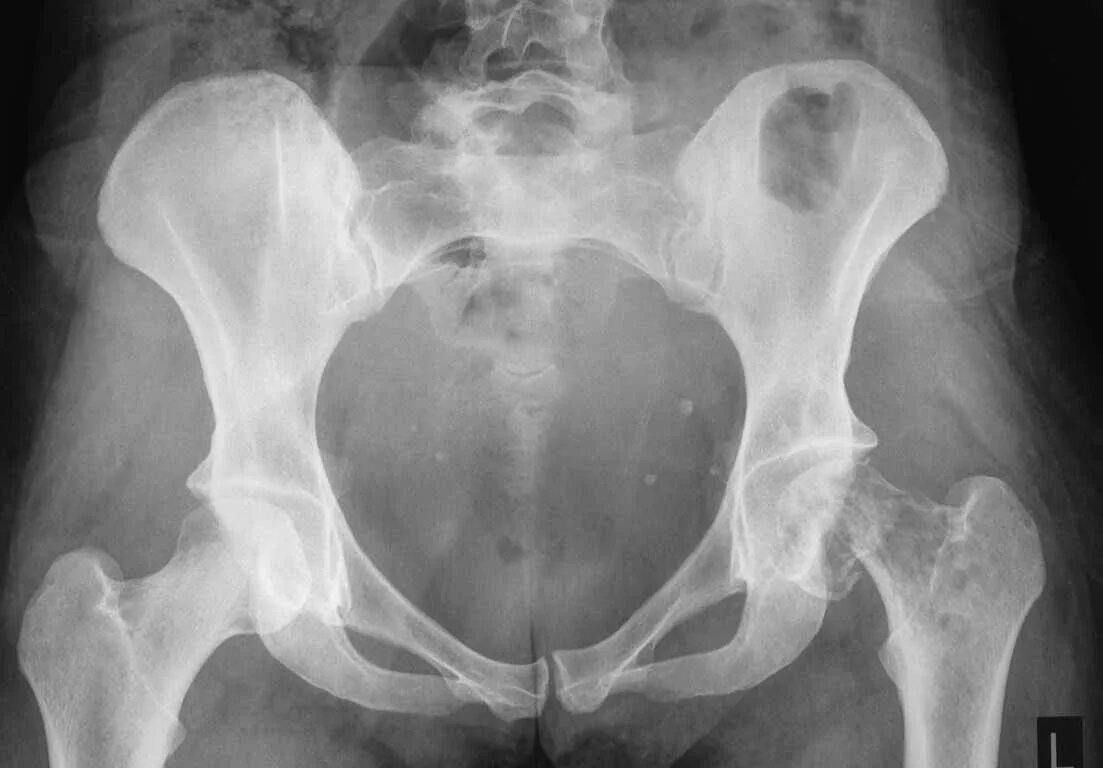

Перелом тазобедренного сустава в пожилом возрасте